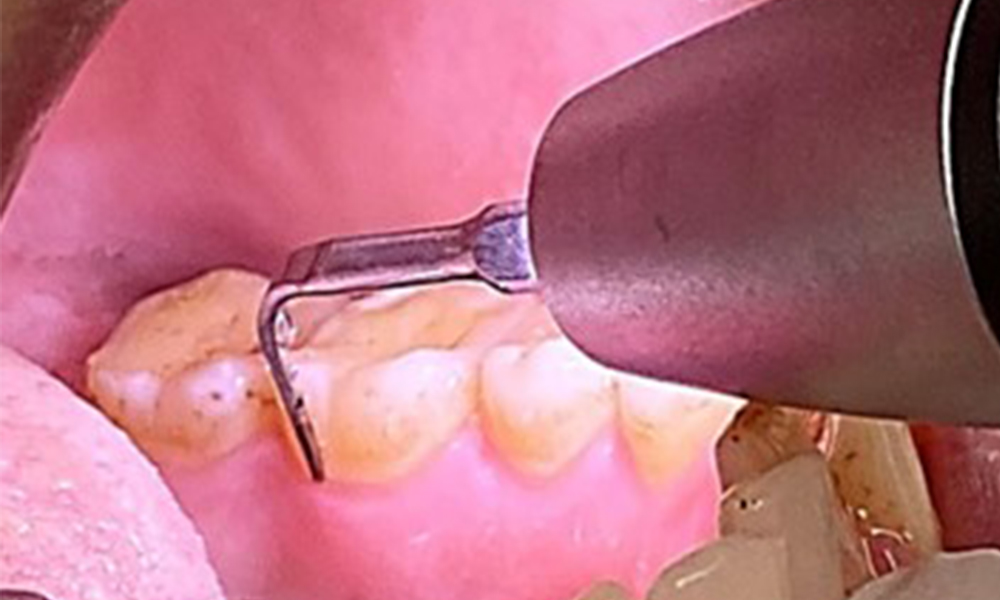

Due to the otherwise favourable general medical condition, the needs determined during the intraoral examination will be decisive for their treatment. It will be essential to periodically determine the probing depths. Gingival bleeding decreases in smokers, which is why the clinical diagnosis of periodontitis can only be made by probing (Fig. 7). Placing exclusive focus on the determination of bleeding indices may obscure existing periodontitis or gingivitis. (5)

Instruction and motivation are important components of these appointments. Good home-based intraoral hygiene behaviour and understanding are important for patients. Plaque accumulation is particularly evident in the cervical regions (Fig. 8).